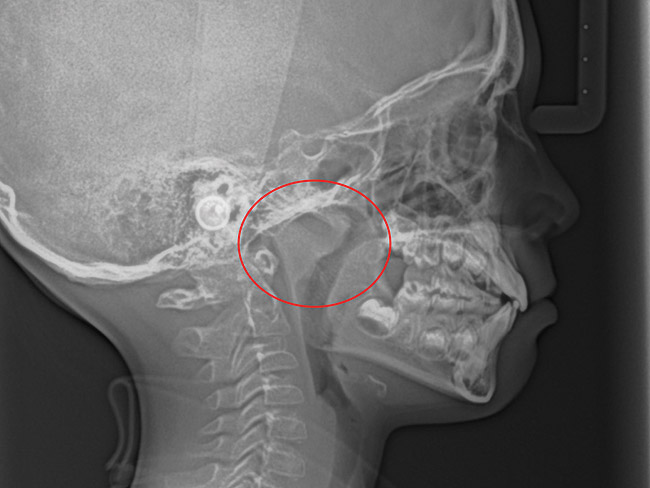

Tonsils and adenoids should be judged against the relative size of the airway rather than the absolute size of the lymphoid tissue46 (Figure 5 and Figure 6). Adenoids are located at the posterior of the nasal cavity on the roof of the nasopharynx (Figure 7). The normal distance from the adenoids to the soft palate for an acceptable airway should be at least 12 mm. For each millimeter decrease, the odds of the child snoring increase 1.61 times. Mouth breathers typically show a smaller upper airway dimension as well.47 The adenoid and tonsillar obstruction creates the trigger, but the deviate facial and neck muscle recruitment and tongue hypotonia cause the maldevelopment.48

(6.) Radiographic evaluation of tonsils. Intraoral examination may not clearly portray the volume of tissue.

Figure 6